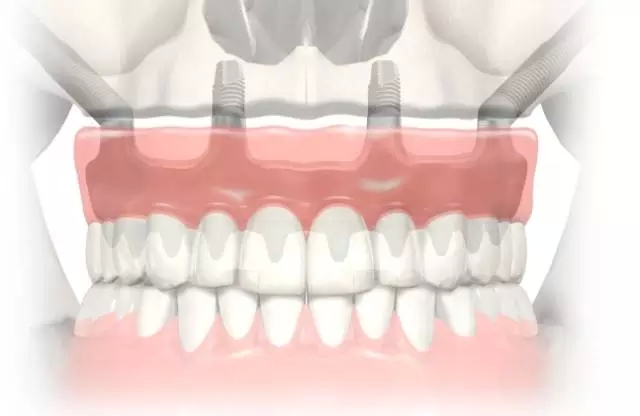

考古研究發(fā)現(xiàn),古埃及宮庭婦女就有采用骨內種植動物牙和象牙雕刻的人造牙的記載,出土的人類頜骨化石中還發(fā)現(xiàn)鑲有寶石或黃金雕成牙體形狀的植入物,它是牙種植體的原始雛形,最早可以追溯到公元前6000年。 中國有記載的種牙歷史比較遲 約800多年前 陸游:“近聞有醫(yī)以補墜齒為業(yè)者。” 800多年前,我國宋代樓鑰所著的《玫瑰集》中,也記載著了種牙。 宋代的大文豪陸游,不僅是一位豪放詩人,也是一位醫(yī)學愛好者。在陸游的《歲晚幽興》中說:“卜冢治棺輸我快,染須種牙笑人癡。”更可貴的是,他還在詩后面加了自注:“近聞有醫(yī)以補墜齒為業(yè)者。” 為了口腔健康,世界各國的人們想盡了辦法! 公元前4世紀,古希臘人就用人牙、動物牙、黃金和木材料來做人的假牙。 意大利西北部的伊特拉斯坎人在公元前700年就開始制作假牙,然后用金制箍條固定在鑲牙者口中。 在18世紀曾有從事“獵牙”者。1815年的滑鐵盧戰(zhàn)役留下的巨大牙齒資源,那一仗,拿破侖損失了3萬將士,英普等聯(lián)軍損失了2.3萬將士,這幾萬套“滑鐵盧牙齒”整整服務了歐美一代鑲假牙的人。 為了一顆好牙,人類的道德底線被擊穿了。 曙光與低谷 30年代至60年代的徘徊不前 1947年,M. formiggini以鉭絲錐形體植入口腔頜骨 1947年,M. formiggini以鉭絲錐形體植入口腔頜骨,成功地完成了義齒修復,他被譽為口腔種植學的奠基人,口腔種植技術似乎看到了曙光。 但由于在五六十年代種植義齒的臨床應用過分超前于基礎研究,造成種植高失敗率。1973年,國際衛(wèi)生研究所和美國牙醫(yī)學會的牙科材料委員會經(jīng)調查,對種植義齒持否定態(tài)度,牙種植由此一度跌入低谷。 終于找到開啟金色大門的鑰匙 1952-1982年,現(xiàn)代口腔種植學開啟 1952年,Br?nemark發(fā)現(xiàn)骨和純鈦能發(fā)生結合, 基礎研究的突破帶來了質的飛躍 20世紀60年代,Br?nemark教授首次提出口腔植入體使用高純度的鈦金屬替代以往的黃金等貴金屬成為新的植入材料。他在動物實驗中發(fā)現(xiàn),骨組織與植入的純鈦種植體結合得異常牢固,形成了一個完美的整體。 基于此項研究結果,Br?nemark教授創(chuàng)立了全新的骨結合理論:即人體活的骨組織與鈦種植體之間發(fā)生牢固、持久而直接的結合。該理論的確立在種植體領域掀起了革命性的變化。 在有記載的7000多年口腔種植歷史中,人類一直站在這扇厚重的金色大門前,束手無策。Br?nemark教授重于找到了開啟金色大門的鑰匙,人類正式步入現(xiàn)代口腔種植學的殿堂。 在這30年中 Br?nemark教授和他的團隊 克服了無數(shù)的困難與質疑 由于厚積了幾千年的失敗經(jīng)驗,物理學家和牙醫(yī)們思想已經(jīng)被牢牢固化。他們認為非生物材料不可能融入活的生物組織——最初的炎癥和最終的排異是不可避免的,這個過程也會給病人帶來極大的痛苦。 Br?nemark教授的發(fā)現(xiàn)有悖“傳統(tǒng)智慧”,因此,即使在1965年Br?nemark教授為G?sta Larsson先生成功的進行了鈦種植體種入,前方的路途依然漫長而坎坷。 現(xiàn)代口腔種植學的起源一方面來自骨結合理論的確立,另一方面還源于Br?nemark教授建立起的現(xiàn)代口腔種植標準化操作流程,他所著的《OSSEOINTEGRATED IMPLANTS》一書是現(xiàn)代口腔種植學的第一座里程碑。 在1982年多倫多召開的牙科種植大會上,Br?nemark教授向與會者展示了其團隊在齒科種植體領域15年的工作成績。從骨結合理論的發(fā)現(xiàn)與應用,到大量的、全新整理的科學實驗數(shù)據(jù)以及世界第一例成功種植牙臨床病例,終于獲得了與會者廣泛的關注和認可。 1982年多倫多召開的牙科種植大會 向Br?nemark教授和他的團隊致敬! 在金色大道上高歌前行 Nobel Biocare 時代來了 1978年,諾貝爾工業(yè)集團與Br?nemark教授開始合作,1981年Nobelpharma AB公司成立,1996年,公司更名為今天的Nobel Biocare公司。 一 Br?nemark System® Nobel Biocare經(jīng)久耐用的Br?nemark System®,G?sta Larsson先生使用了該系統(tǒng),運行40年依舊穩(wěn)固如新。 二 NobelReplace® Tapered Replace Select™ Tapered NobelReplace® Tapered(諾保易配錐形)及Replace Select™ Tapered(易配精選錐形)模仿自然牙根的形狀,該設計在所有負重方案,包括即刻行使功能中,都能取得極高初始穩(wěn)定性。 更新、更領先的系統(tǒng) NobelReplace® CC (Conical Connection) NobelReplace® CC (Conical Connection)結合獨創(chuàng)的錐形種植體主體和緊密密封的錐形連接體,為您和您的患者提供了一種適用于所有適應證的美齒解決方案。種植體主體可模擬自然牙根的形狀,旨在實現(xiàn)各種負重治療方案(包括 Immediate Function-即刻行使功能)的較高初期穩(wěn)定性。 NobelReplace® CC (Conical Connection)2011年全球上市(2015年中國上市)。 三 NobelActive® NobelActive®是具有劃時代意義的種植體。其體部及螺紋設計可以在植入時使進行骨擠壓,即使在骨質受損的情況下,也可以獲得很高的初始穩(wěn)定性。這使之成為即刻種植的理想之選。另外,頂部帶鉆刃的反向切割槽,可以調整種植體方向,以獲得最佳修復方向。 NobelActive®2008年全球上市(2012年中國上市)。 四 NobelSpeedy®系統(tǒng) NobelSpeedy®系統(tǒng)即使在軟質骨中使用也有很高的初始穩(wěn)定性,操作高效省時,同時具有卓越的多功能性和享受修復靈活性,特別是在快速骨形成的愈合時期保持很高的穩(wěn)定性,確保長期成功。 All-on-4®治療概念由帶有外六角的NobelSpeedy®種植體發(fā)展而來。 什么是 All-on-4® 概念? 開發(fā) All-on-4 臨床解決方案的目的在于最大限度地利用可利用骨量并支持即刻負重。 四顆種植體支撐全口無牙頜: 2顆前牙種植體,直的 2顆后牙種植體,傾斜的 全口樹脂牙橋進行即刻、臨時、固定修復與負重。 All-on-4®是NobelBiocare的注冊商標